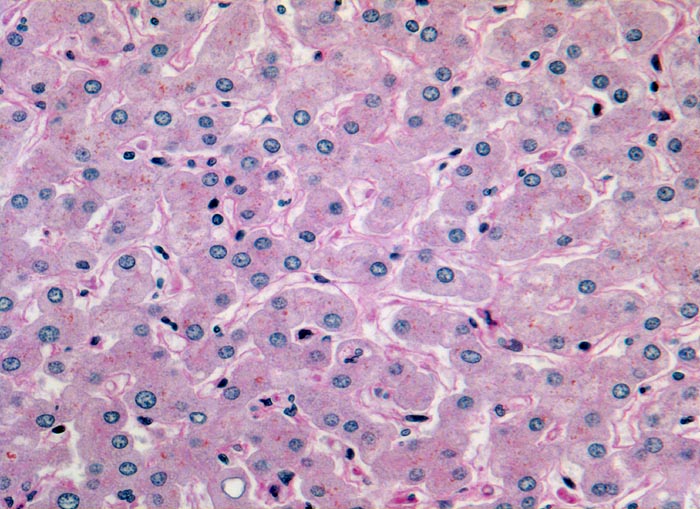

PathoPic – image database / PathoPic ID 3130 - Normales Leberparenchym

Normales Leberparenchym

Ein- bis zweireihige Leberzellplatten. Dazwischen Sinusoide. In den Sinusoiden sind die Kerne von Endothelzellen und Kupffer'schen Sternzellen erkennbar. Das feinkörnige braune Pigment in den Hepatozyten entspricht Lipofuscinpigment.

Histologie

200